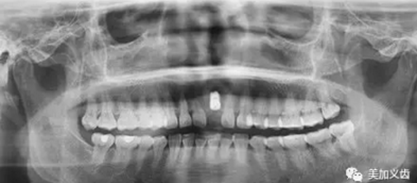

3.牙科CT掃描,種植計(jì)劃

頜面部CBCT掃描,頜骨三維建模。在CBCT數(shù)據(jù)處理軟件中標(biāo)記出重要的神經(jīng)、血管、上頜竇等關(guān)鍵解剖標(biāo)志。將上述CAD/CAM軟件中完成的冠橋CAD數(shù)據(jù)導(dǎo)入CBCT軟件,.STL格式的牙頜模型與DICOM格式的CT牙頜骨模型配準(zhǔn)整合,選擇合適的植體,避開(kāi)重要解剖結(jié)構(gòu),設(shè)計(jì)安全的種植體植入位置與角度,實(shí)現(xiàn)以生理性修復(fù)為導(dǎo)向的種植規(guī)劃。